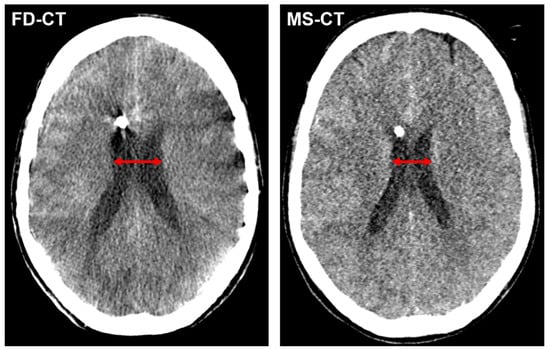

3.4.1. Cella Media Distance